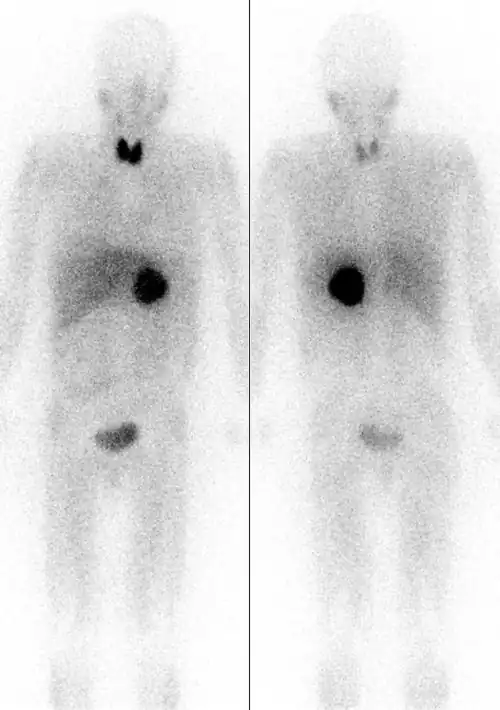

Links: von vorne. Rechts: von hinten.

Wenn die Bestimmung der Plasma-Metanephrine wiederholt ein positives Ergebnis bringt, muss eine weiterführende Lokalisationsdiagnostik durchgeführt werden. Dies geschieht mittels bildgebender Verfahren wie Computertomographie und Sonographie oder MRT-Bildgebung. Bei der CT ist zu berücksichtigen, dass beim Einlaufen von Jod-Kontrastmittel Katecholamine ausgeschüttet werden können, was bei der MRT nicht der Fall ist. Die nuklearmedizinische Methode der MIBG-Szintigrafie (Metaiodobenzylguanidin) dient vor allem dem Ausschluss von Phäochromozytomen außerhalb der Nebenniere. Diese Substanz lagert sich vornehmlich in den betroffenen chromaffinen Zellen des Phäochromozytoms ab. Die neueste und zuverlässigste Form der nuklearmedizinischen Methode ist bei Phäochromzytomen das so genannte DOPA-PET. Es wird zurzeit (Stand 2012) in Deutschland allerdings lediglich in wenigen Zentren angeboten. Zusätzlich muss auf alle Fälle nach Tumoren eines eventuellen MEN-Syndroms gesucht werden.